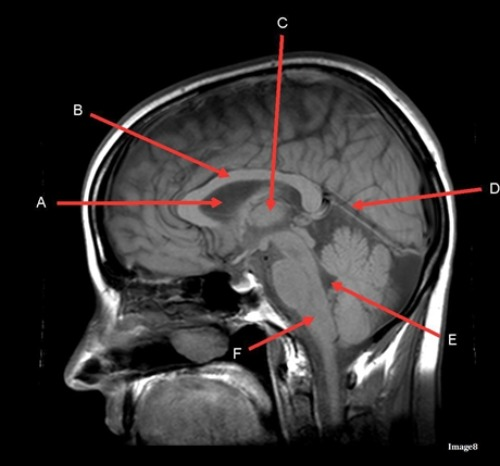

Letter C in image 8 is pointing to:

A. Tentorium

B. Corpus callosum

C. Thalamus

D. Fourth Ventricle

E. Medulla oblongata

Letter D in Image 8 is pointing to:

B. Cerebellum

Letter A in Image 8 is pointing to:

C. Hypothalamus

E. Lateral Ventricle

Image 8 is an example of a ____ weighted sequence acquired in the ____ scan plane.

A. T1; Axial

B. T1; Sagittal

C. T2; Axial

D. T2; Sagittal

Letter A in Image 7 is pointing to:

A. Pons

D. Genu of the corpus callosum

E. Splenium of the corpus callosum

Letter B in Image 7 is pointing to:

Letter C in Image 7 is pointing to:

Letter B in Image 8 is pointing to:

Letter E in Image 8 is pointing to:

Letter F in Image 8 is pointing to: